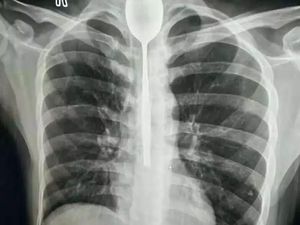

Telan Sendok Demi Taruhan, Sendok Tersangkut di Tenggorokan Selama Setahun

Seorang pria di China, harus dioperasi setelah ia menelan sendok berukuran besar demi sebuah taruhan. Selama satu tahun sendok itu berada dalam tenggorokannya.